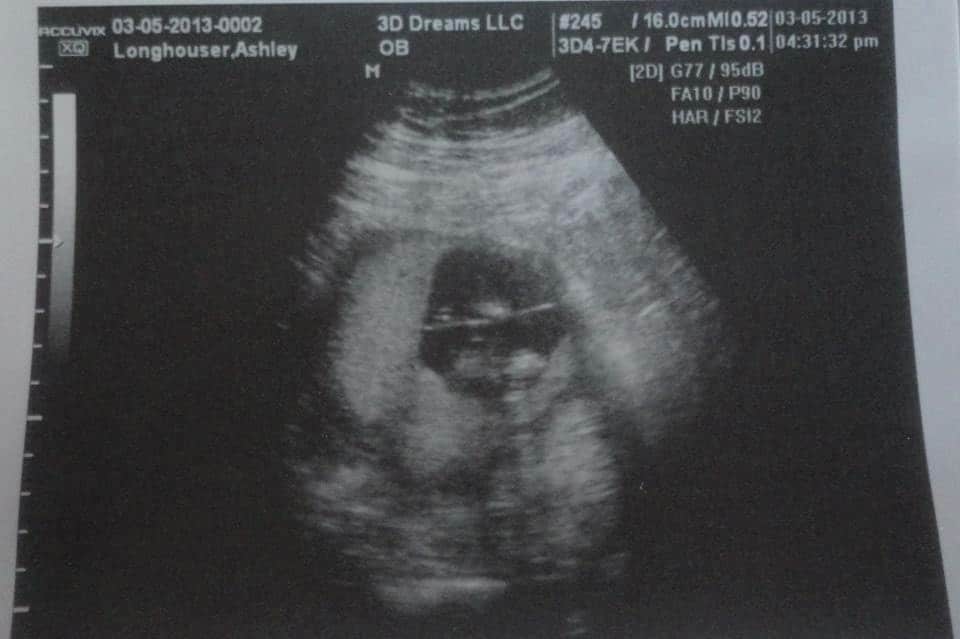

- Ultrasound Photos at 13 Weeks Pregnant With Twin

Ultrasound Photos at 13 Weeks Pregnant With Twin